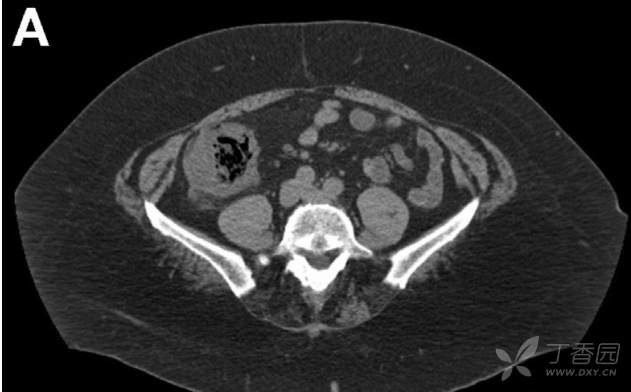

腹部CT平扫提示升结肠肠壁增厚(图A)。患者之前18个月、7个月的肠镜检查及磁共振肠成像均无异常发现。